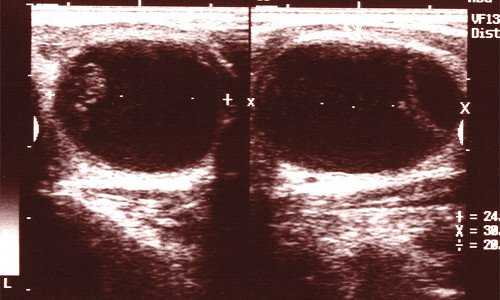

Доброкачественные образования ЩЖ (узлы и кисты) до полового созревания встречаются редко. В большинстве случаев узлы и кисты у подростков доброкачественные, они встречаются в 6-10 раз реже, чем у взрослых (6-7% популяции), но озлокачествляются в 26-30 раз чаще [10, 11]. Самый частый вариант доброкачественного узла у детей и подростков - фолликулярная аденома (рис. 3), представляющая собой результат циклов гиперплазии и коллоидной инволюции фолликулов ЩЖ. Образование имеет четкие контуры, инкапсулировано, чаще всего одиночное, плотность может быть гипо-, изо- или гиперэхогенной. Вокруг часто регистрируется гало, вероятнее всего, за счет сдавливания окружающей нормальной паренхимы. Образование не функционирующее, выявляется случайно или, при больших размерах, клинически при осмотре или пальпации. Резко возникшие боли в месте аденомы и ее быстрое увеличение свидетельство спонтанного кровоизлияния. Окончательная диагностика возможна только по результатам биопсии.

Рис. 3. Аденоматозный узел, практически полностью заменивший долю щитовидной железы.

Доброкачественные образования ЩЖ